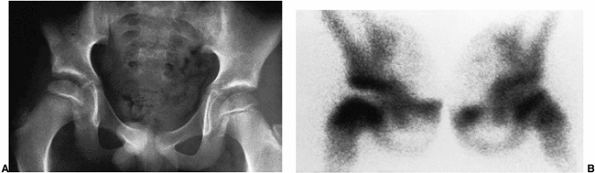

Figure 25.22 An 8-year-old boy with right hip pain. A:

Anteroposterior radiograph demonstrates a slight increase in width and medial joint space; the femoral ossific nucleus is slightly smaller than the one on the opposite side. B: Technetium 99 radionuclide scan demonstrates decreased uptake in the entire right femoral head, with increased vascularity in the neck. |